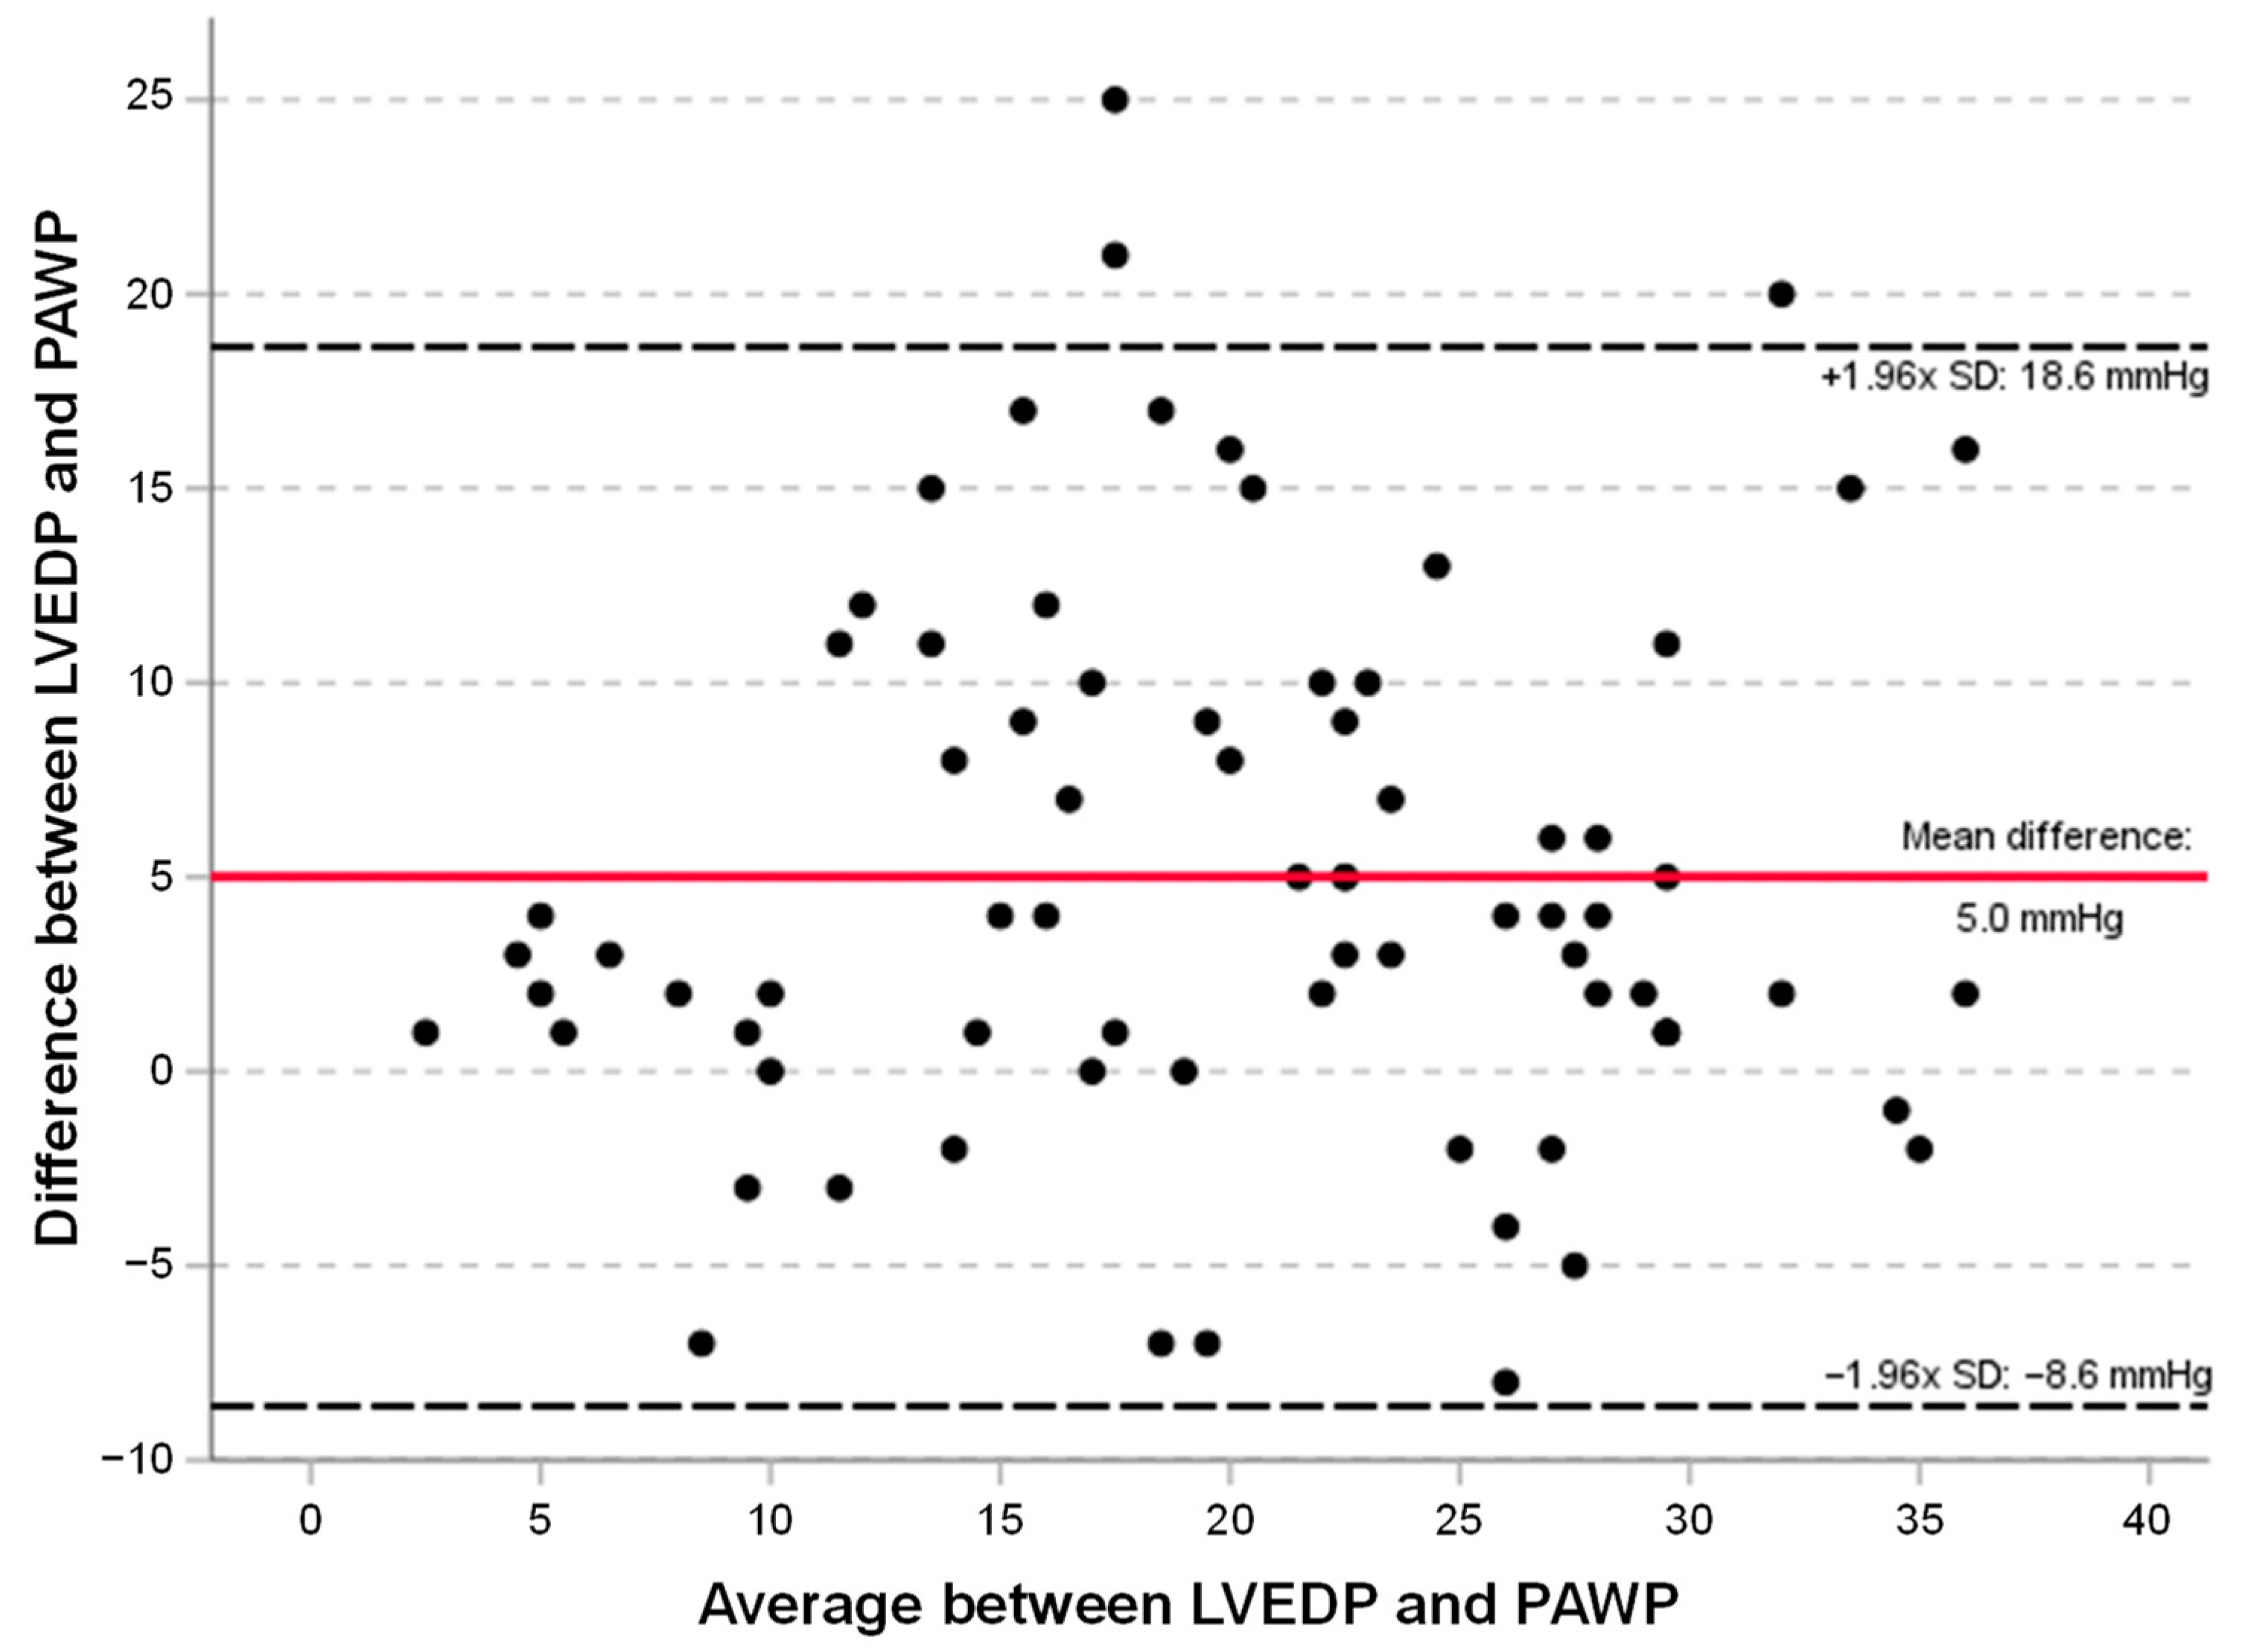

3.3. Correlation of PAWP with LVEDP

3.4. Linear Regression Models